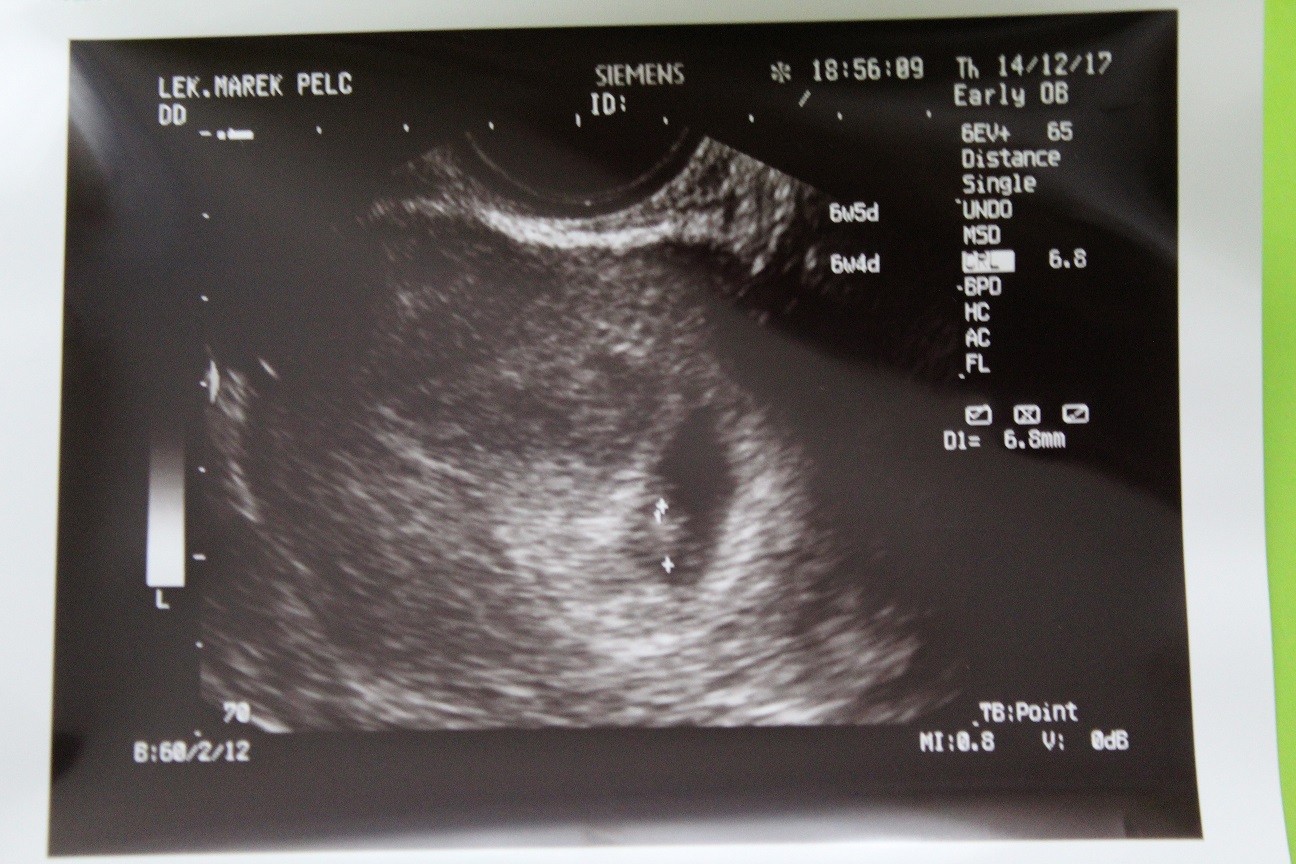

Jakie problemy mogą ujawnić ultradźwięki w tym tygodniu położniczym i jak są rozwiązywane. Do końca tego tygodnia osiągnie rozmiar 7-9 mm. USG w 8 tygodniu ciąży.

Jaka powinna być wielkość płodu i szybkość miednicy. Co można zobaczyć na USG w tym czasie. Jakie funkcje zauważy diagnosta podczas badania USG miednicy.

USG dopochwowe dobrze wykonać po raz pierwszy właśnie w 8 tygodniu ciąży. Dziecko w 7 tygodniu ciąży Serce Twojego maleństwa składa się już z 4 wyraźnych części i bije w regularnym tempie. Nie jest to związane z wielkością samej macicy którą można porównać do grejpfruta ale raczej z poluzowaniem.

Widoczne są już malutkie jeszcze zrośnięte paluszki u rąk kształtują się nerki. 7 tydzień ciąży wielkość zarodka. Ósmy tydzień to odpowiedni czas na wykonanie USGZarodek na pewno zdążył się już zagnieździć lekarz będzie mógł też przyjrzeć się pracy serduszka serce bije z zawrotną prędkością 150 uderzeń na minutę.

Tydzień ciąży Twoje dziecko w 8. Chowa się ogonek dzięki któremu był porównywany do konika morskiego. W 8 tygodniu ciąży podczas badania USG można już dostrzec kręgosłup.